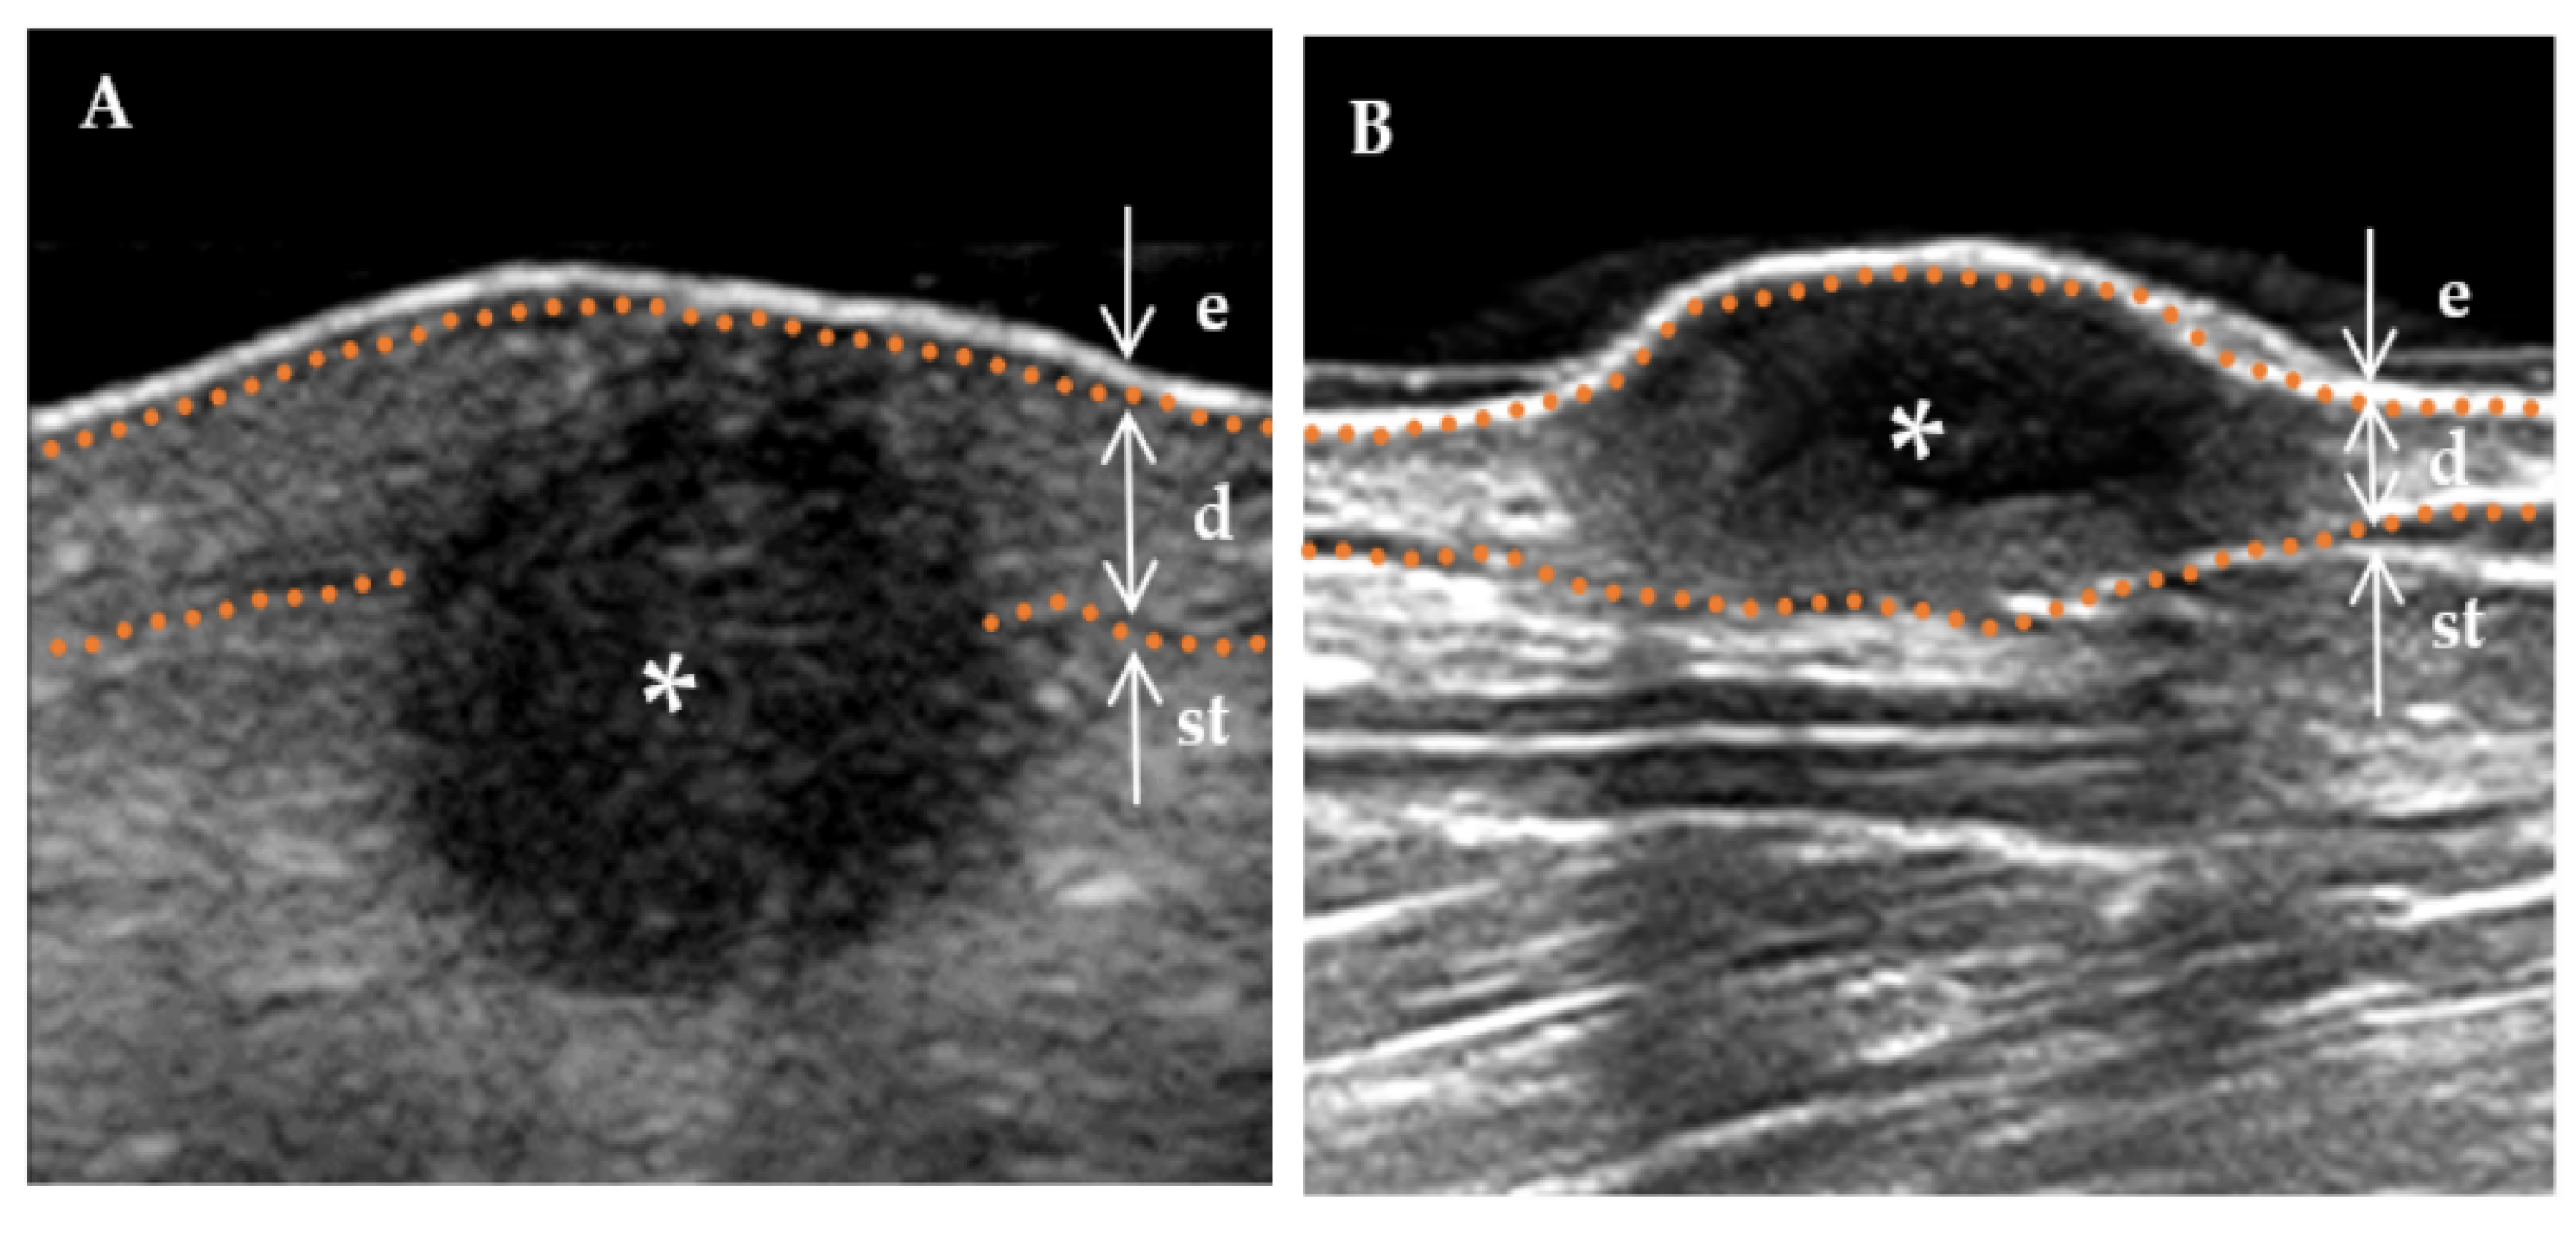

Figure 3.

The internal echogenicity of DF lesions. * Indicates the precise location of the lesion on the ultrasound image. The skin layers are indicated by dotted orange lines, with arrows indicating a hyperechoic epidermis (e), an isoechoic dermis (d), and a subcutaneous tissue (st). (A) The internal echogenicity of the mass is homogeneously distributed: the mass exhibits a homogeneous low echogenicity pattern with similar echogenicity distribution in any direction. (B) The internal echogenicity of the mass is heterogeneously distributed: the core of the mass is hypoechoic compared to the cortex (cortical portion), which is more echogenic.